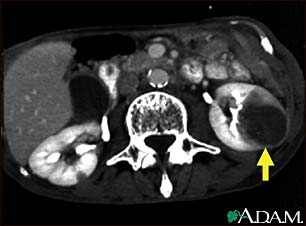

Kidney metastases, CT scan

A CT scan of the middle abdomen showing metastasis (cancer that has spread) in the left kidney in a patient with carcinoma of the lung. Note the large dark circular tumor in the kidney on the right side of the picture.